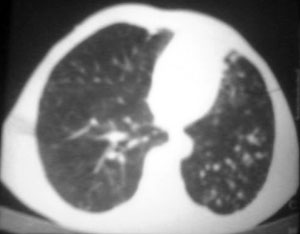

以下是引用逸风在2006-9-12 14:57:00的发言:[br]ct显示双肺上叶点片状及纤维索条状密度不均影,肺野外带近胸膜可见大小不等的含气空腔,壁略厚,境界清晰,未见液平面,中下肺野散在小片状及点状高密度影;纵隔内显示点状钙化,未见明显淋巴结肿大,构成胸廓诸骨未见明显异常.[br]诊断意见:1.双肺结核合并支气管播散;2.双肺上肺大泡.